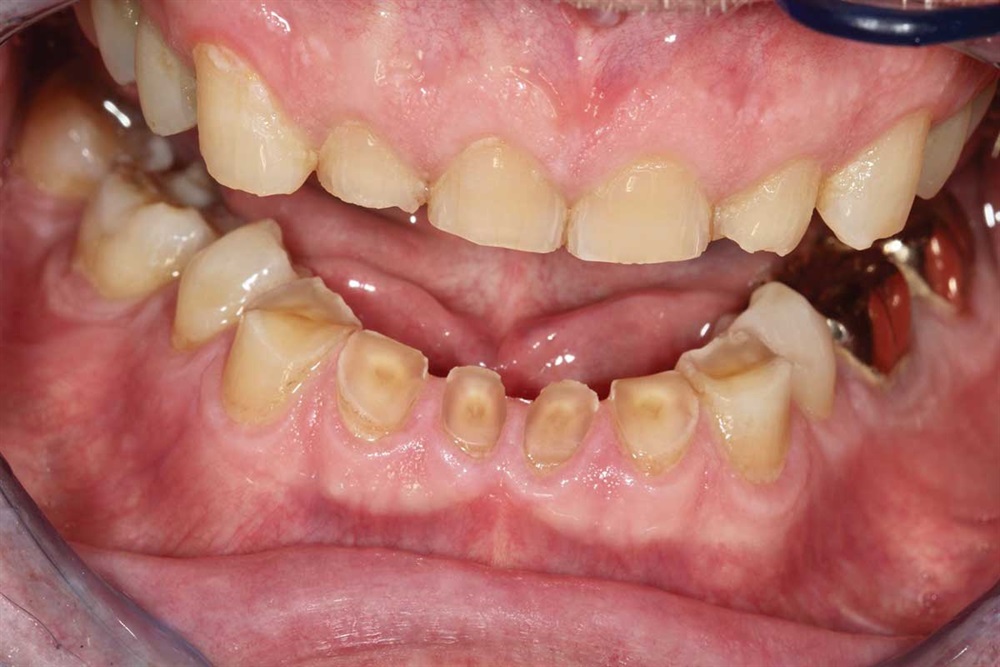

Fig. 1: June 2018. Where did all the tooth structure go? Grinding in protrusion? There is serious wear and tear. This 63-year-old gentleman has been wearing out his teeth, especially in the past 10 years.

Fig. 3: Lower incisors. The patient’s dentists in Ontario wanted to do ortho for 18–24 months and then restorative crowns with many elective root canals, to the tune of a nice luxury car.